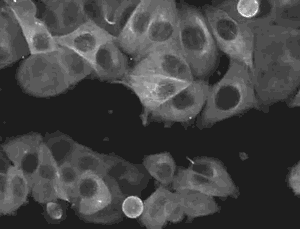

那么什么是间充质干细胞呢?间充质干细胞是干细胞家族的成员,具有自我复制能力和强大分化潜能。同时,间充质干细胞拥有其他干细胞所没有的优点,那就是它还独有向损伤组织定向迁移并根据具体环境来调节免疫反应的能力,这使其在临床应用上表现了巨大的潜力。针对间充质干细胞的这些特性,目前国内外的科学家们已经在间充质干细胞领域开展了深入的科学研究,以期充分了解和认识它强大的可塑性。